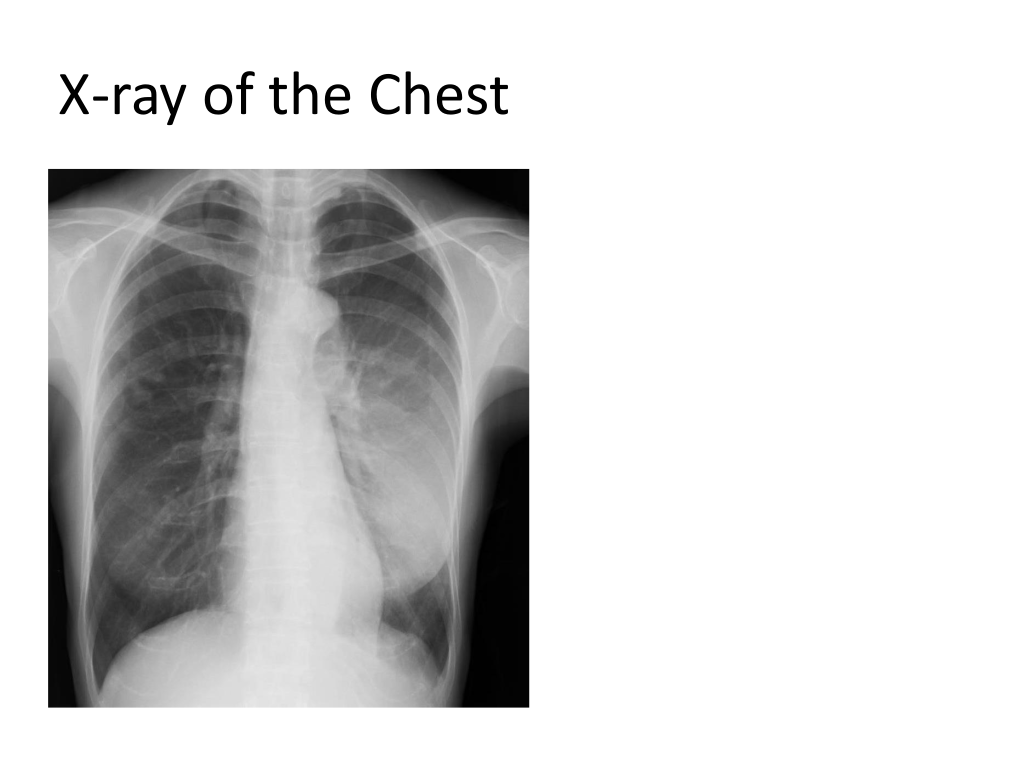

X-ray of the Chest

CT Scan of the Chest CT scan revealed hyperdense infiltrate in the left lung accompanied by air bronchograms. Diagnosis was made for pneumococcal pneumonia. The patient was hospitalized, and treatment was initiated.